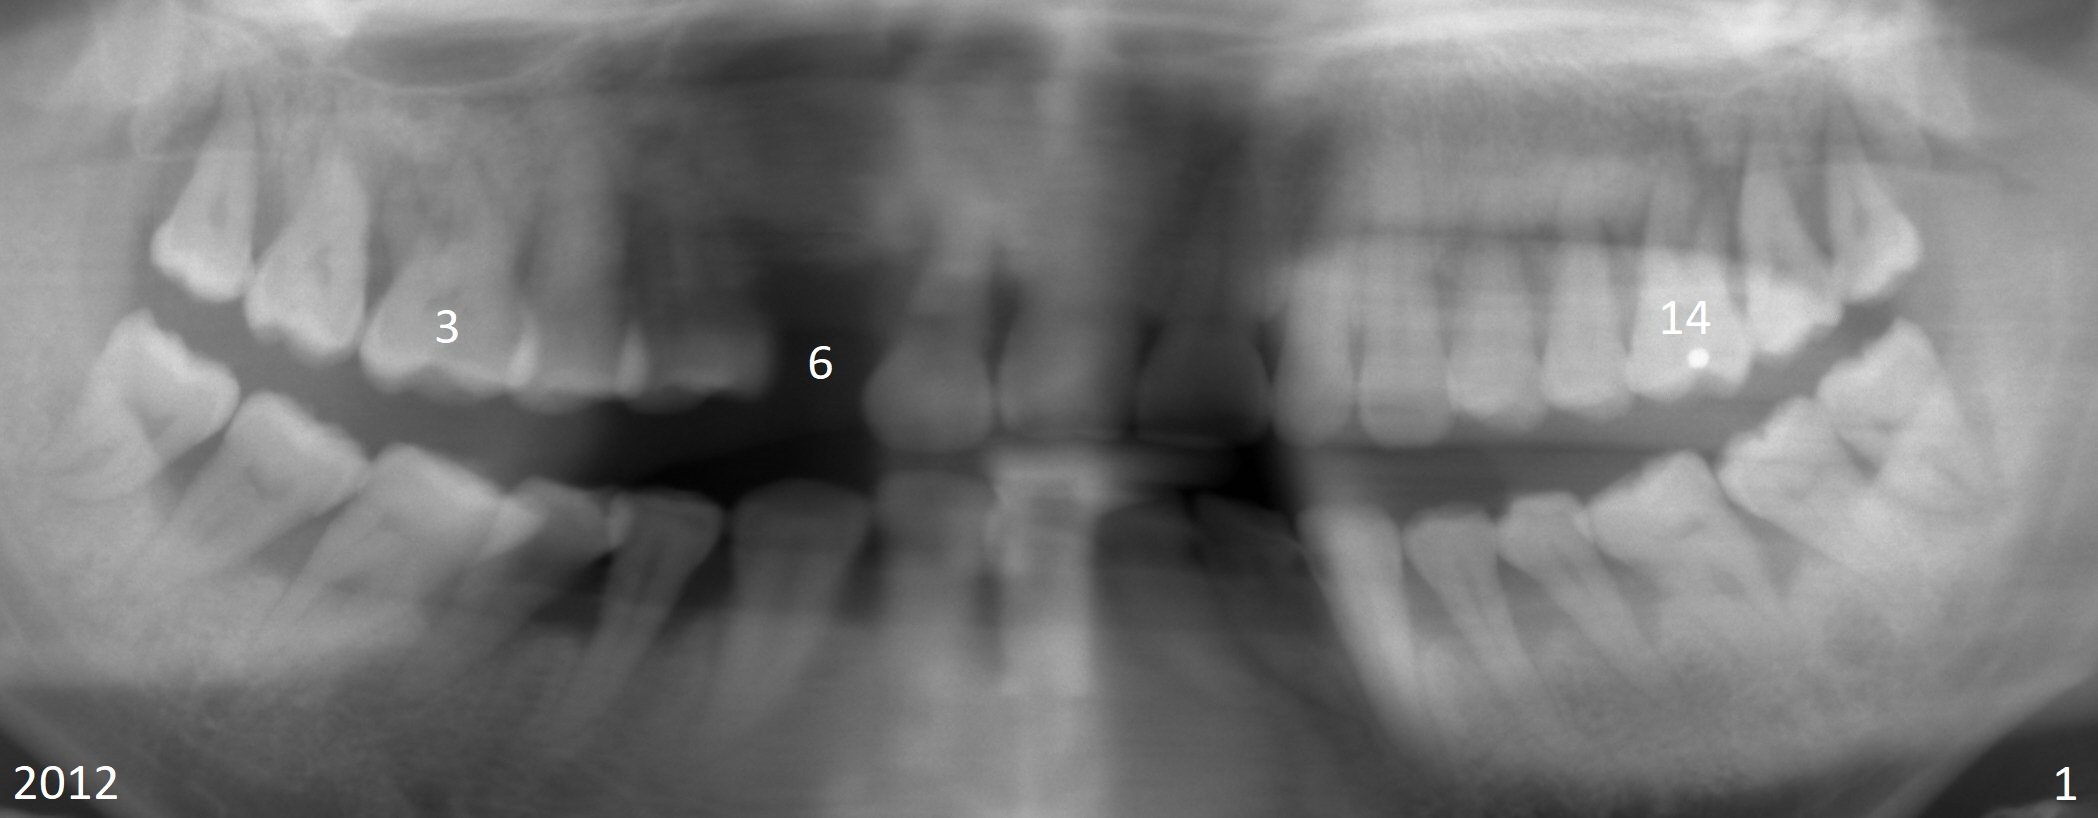

A 48-year-old woman has generalized moderate localized (#3,14) advanced periodontitis (Fig.1). The edentulous area at #6 has been restored. Now the tooth #3 has mobility III (Fig.2), while #14 has exfoliated (Fig.3,4). If the tooth #3 is symptomatic, extract it for immediate implant. Otherwise use Magic Split to initiate access and osteotomy expansion, followed by Magic Expanders (3.0 and 3.8 mm) or Magic Sinus Lifter. Insert Tatum tapered taps. If the gingiva is excessively long, switch to UF implant for mill abutment.